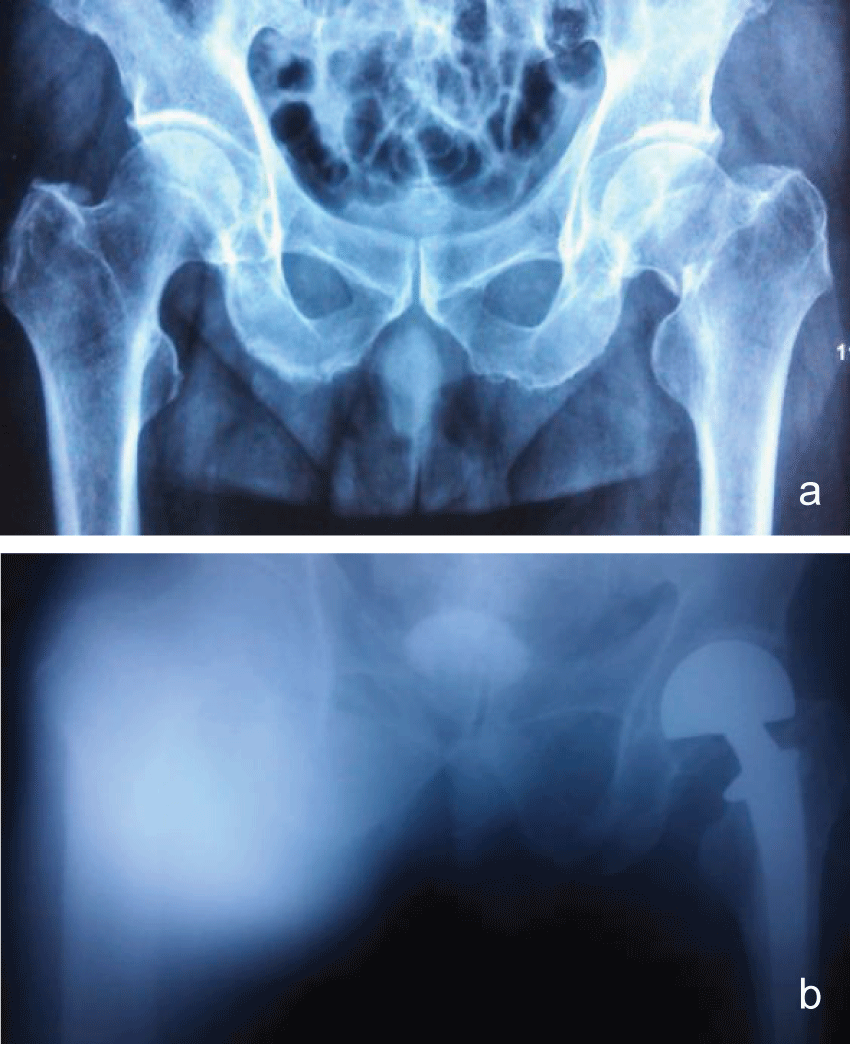

Physical examination of the inflamed limb revealed a discolored and oedematous femoral region, increased temperature when compared with the contralateral limb and pus oozing from a recent puncture site at the affected site. The pain in the affected limb during physical examination was out of proportion to the external physical appearance of atypical cellulitis. Based on the above, the decision to proceed to the operating room was taken and the initial aggressive and wide surgical debridement led to the evacuation of an extended pus collection in the superior anterior femoral muscular compartment and the removal of necrotic muscle tissue (myonecrosis affected the middle head of the quadriceps muscle mostly). The evacuated necrotic tissue area was in direct contact with the femoral vessels. Tissue samples and cultures were taken and sent to the microbiology department. Vacuum sealing drainage device was applied to the traumatic site (Figure 1a and Figure 1b).The patient was subsequently admitted to the surgical ward to support the basic life systems and monitor the response to therapy.

Figure 1: a) Infection after THA; b) VSD was performed; c) VSD was removed and incision was sutured with drainage; d: Infection was recovery.

Under general anesthesia with endotracheal intubation, the patients were placed lateral position. After routine disinfection, the skin was incised along the distal end of original incision, which included the ulcerated wounds. Probing the wound and thorough debridement were performed to remove the infected tissue and pus. During the procedure, several samples were sent for culture and sensitivity tests, and histological evaluation. Then the wound was washed repeatedly with large quantities of saline solution and hydrogen peroxide. After initial extensive debridement wounds were filled with a Poly (vinyl alcohol) shrink formaldehyde bubble using porous silicone drainage tube according to the wound size. The Poly (vinyl alcohol) shrink formaldehyde bubble was stuck to the healthy skin, and the wound was then closed with Poly amino acid ethylester films (Figure1a and Figure 1b).